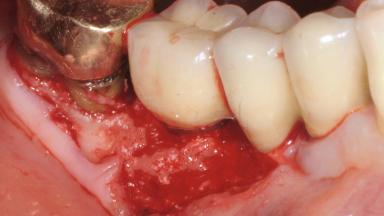

Reconstructive Treatment of a Peri-Implantitis Defect at an Implant in a Mandibular Molar Site

In this case, Mario Roccuzzo utilizes surgical bone regeneration treatment around implant 46 using a bone graft substitute and a connective tissue graft to resolve peri-implant inflammation, reduce the probing depths, and prevent further progression of disease.